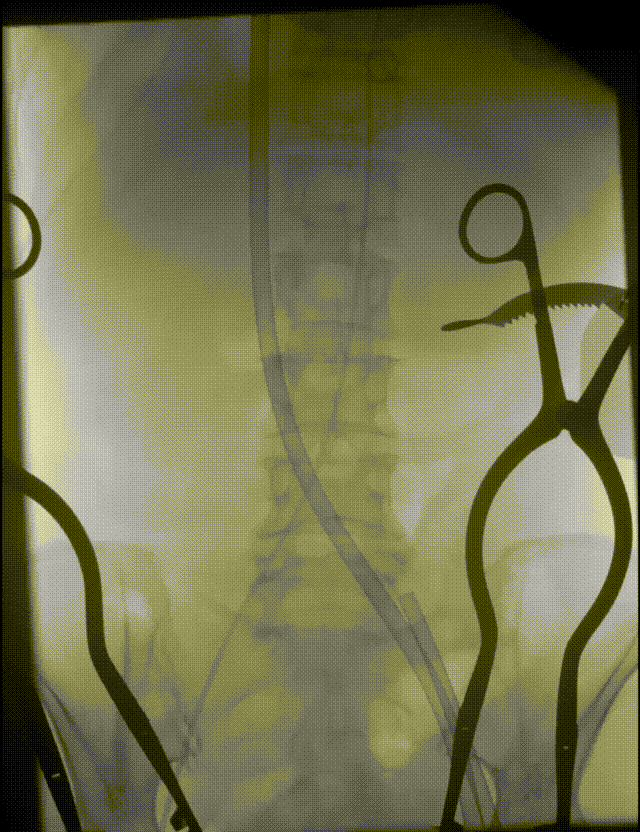

选择18mm球囊预扩,可见造影剂渗漏

Snare辅助植入TF25号瓣膜,瓣膜可见压缩

术中影像

TF25号瓣膜初始定位

全展开评估,瓣膜位置可,形态可见压缩

左侧位评估

瓣膜瓣下2mm左右